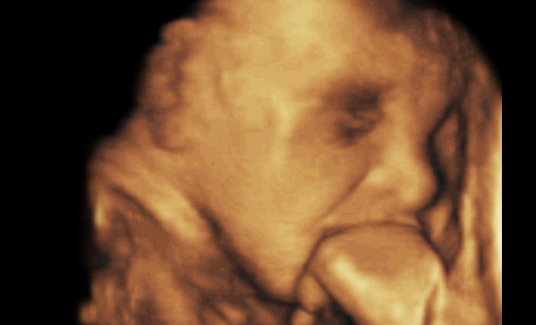

宝宝4D写真